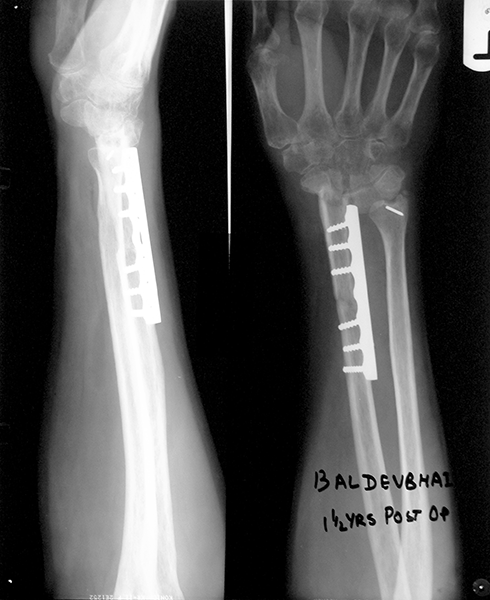

Case:2 GCT-L/E Radius

Pre-Op

Post-Op AP

Post-op Lateral